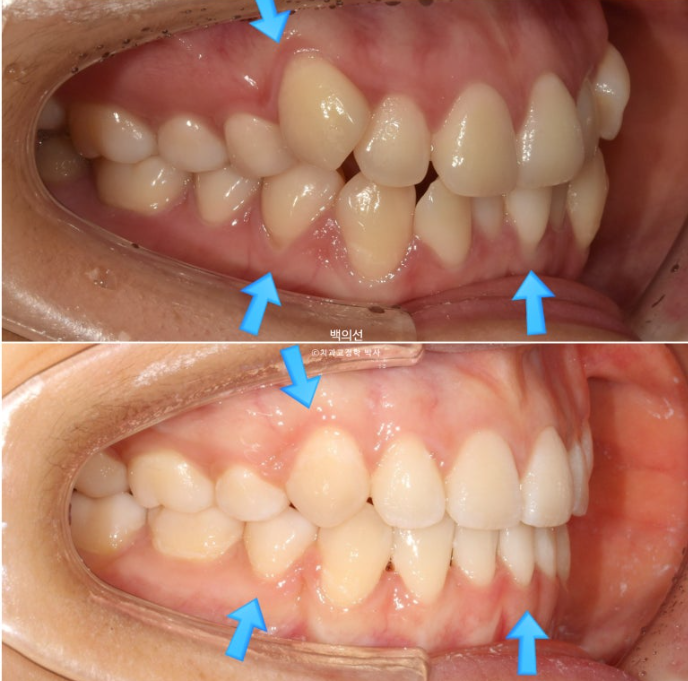

초진 입매를 보면 입술돌출은 거의 없지만 상기의 이유로 작은어금니 4개 발치교정을 결정하였습니다

환자분은 치주건강상의 이슈로 발치의 이유는 납득을 하지만 발치로 인해 입이 너무 들어가지 않게 해달라고 요청하셨습니다.

치료 기간 내내 앞니가 뒤로 들어가는 것을 최소화 하고자 발치공간으로 어금니를 하나씩 앞으로 당겨오는 치료를 했습니다.

전반적으로 입매는 잘 유지가 되었습니다.